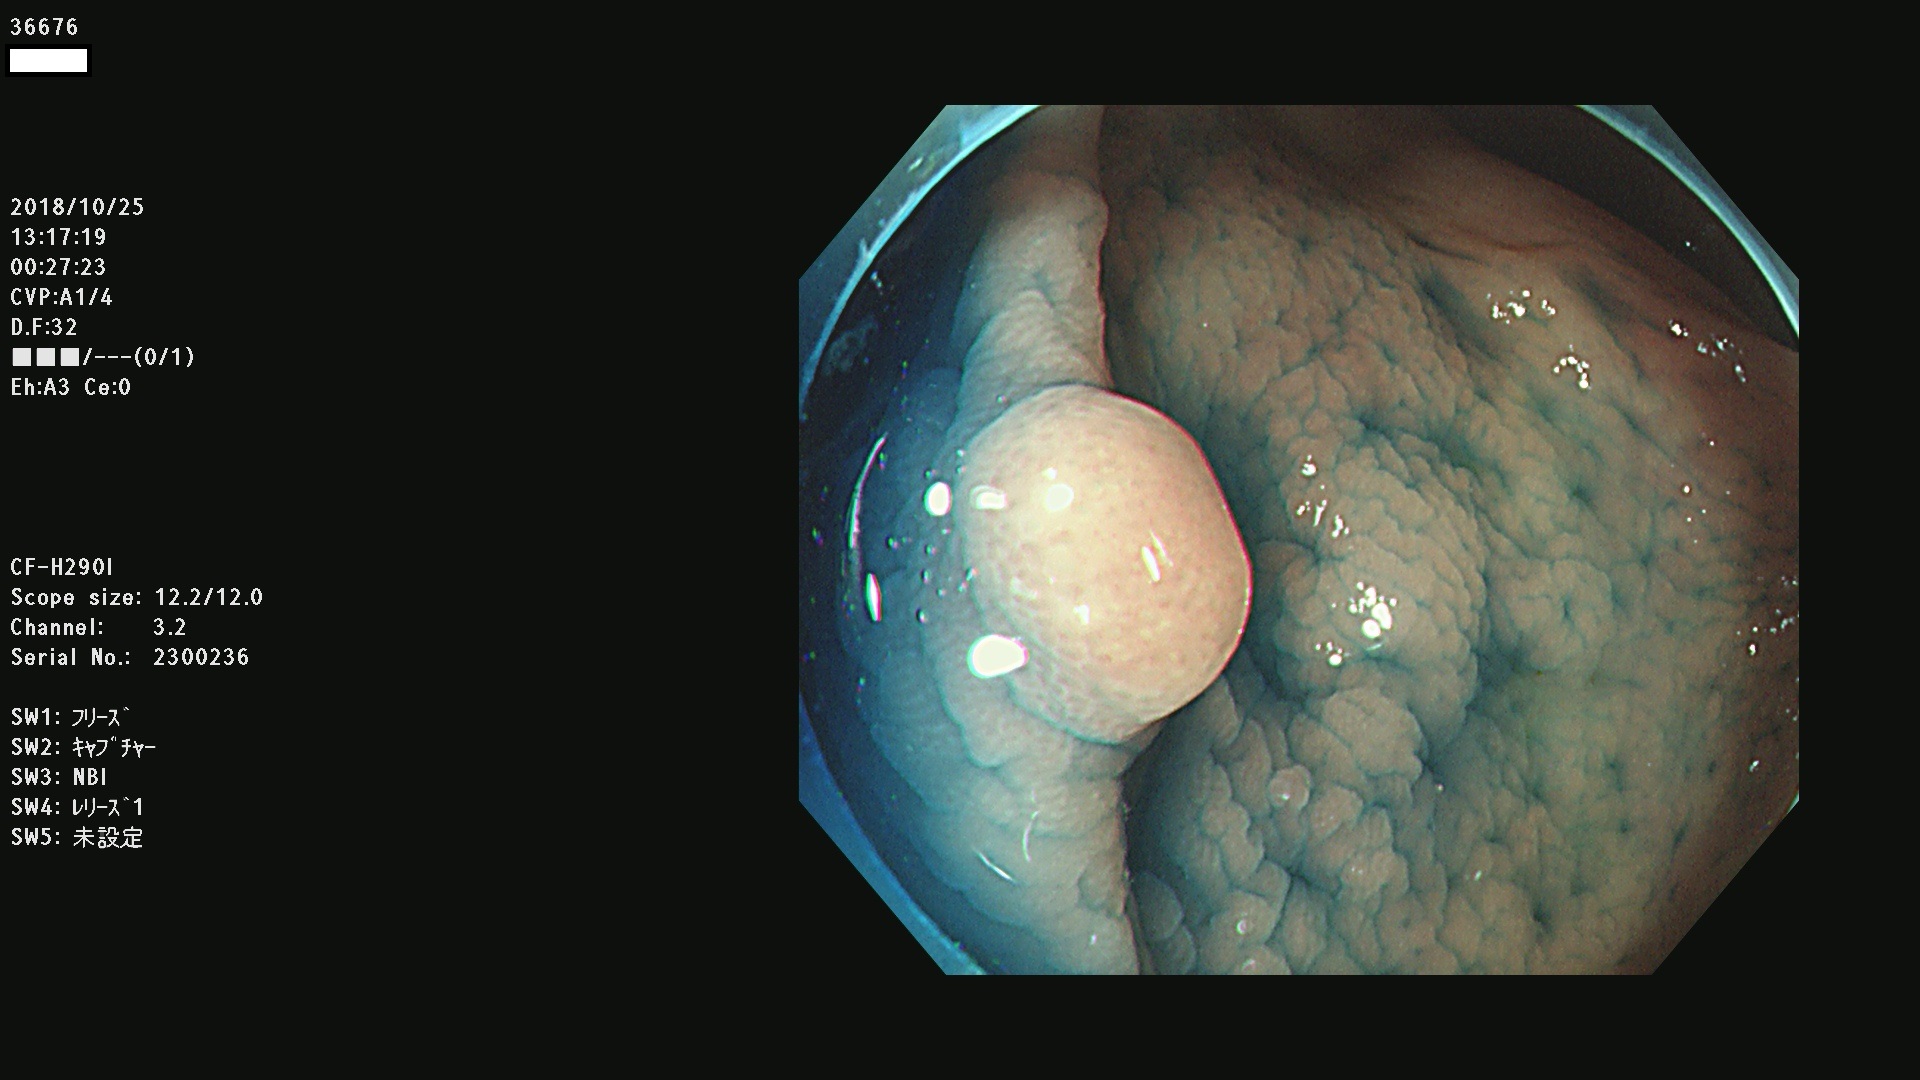

発見困難で危険性の高い平坦型病変(上記100名より抽出)

36600 36601 36603 36605 36606 36608 36609 36610 36611 36612 36613 36615 36617 36620 36621 36624 36625 36626 36627 36628 36629 36631(SSAPのみ) 36632 36633 36634 36636(SSAPのみ) 36637(SSAPのみ) 36639 36640 36642 36643 36644 36646 36647 36648 36649(SSAPのみ) 36650(SSAPのみ) 36652 36653 36654 36655(SSAPのみ) 36656 36657 36658 36659 36660 36661(SSAPのみ) 36665 36668 36669 36672 36673 36676 36677 36678 36679 36681 36682 36683 36684 36685 36687(SSAPのみ) 36691 36692 36693 36694 36695 36696 36697 36699(SSAPのみ)